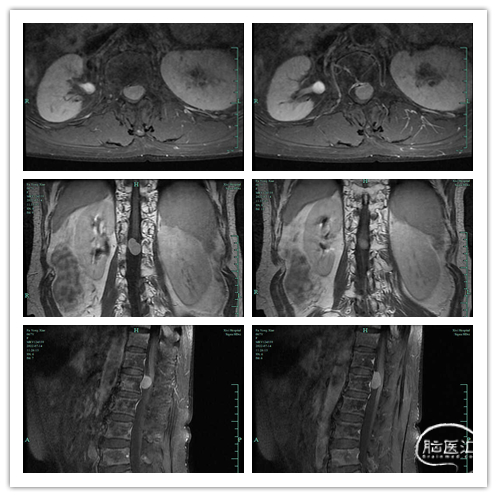

腰椎MRI提示:平L1水平椎管内髓外硬膜内可见一结节状占位灶,边界清楚,大小约1.7*1.2cm,T1WI等T2WI稍高信号,明显均匀强化,肿块局限于椎管偏左侧部,未见向椎间孔延伸。脊髓被挤,信号可。1. L1水平椎管内占位,脊膜瘤首先考虑;2. 腰椎退行性变。

图1. 术前MR